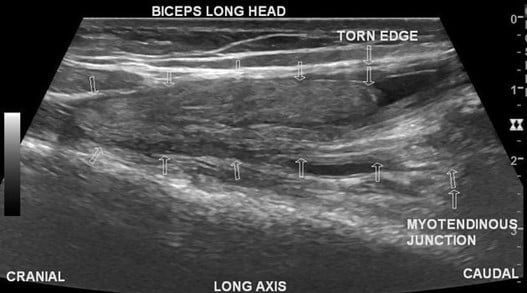

In patients with a long head biceps tear (LHBT), there may be a distinct demarcation of the distal muscle belly, known as a “Popeye” deformity (see Figure 5). On ultrasound, it appears as you move caudally towards the shoulder in the long axis, you will notice disruption of the tendon away from the glenoid with a fluid filled space (see Figure 6).

Figure 6 - Rupture of long head of biceps tendon on ultrasound